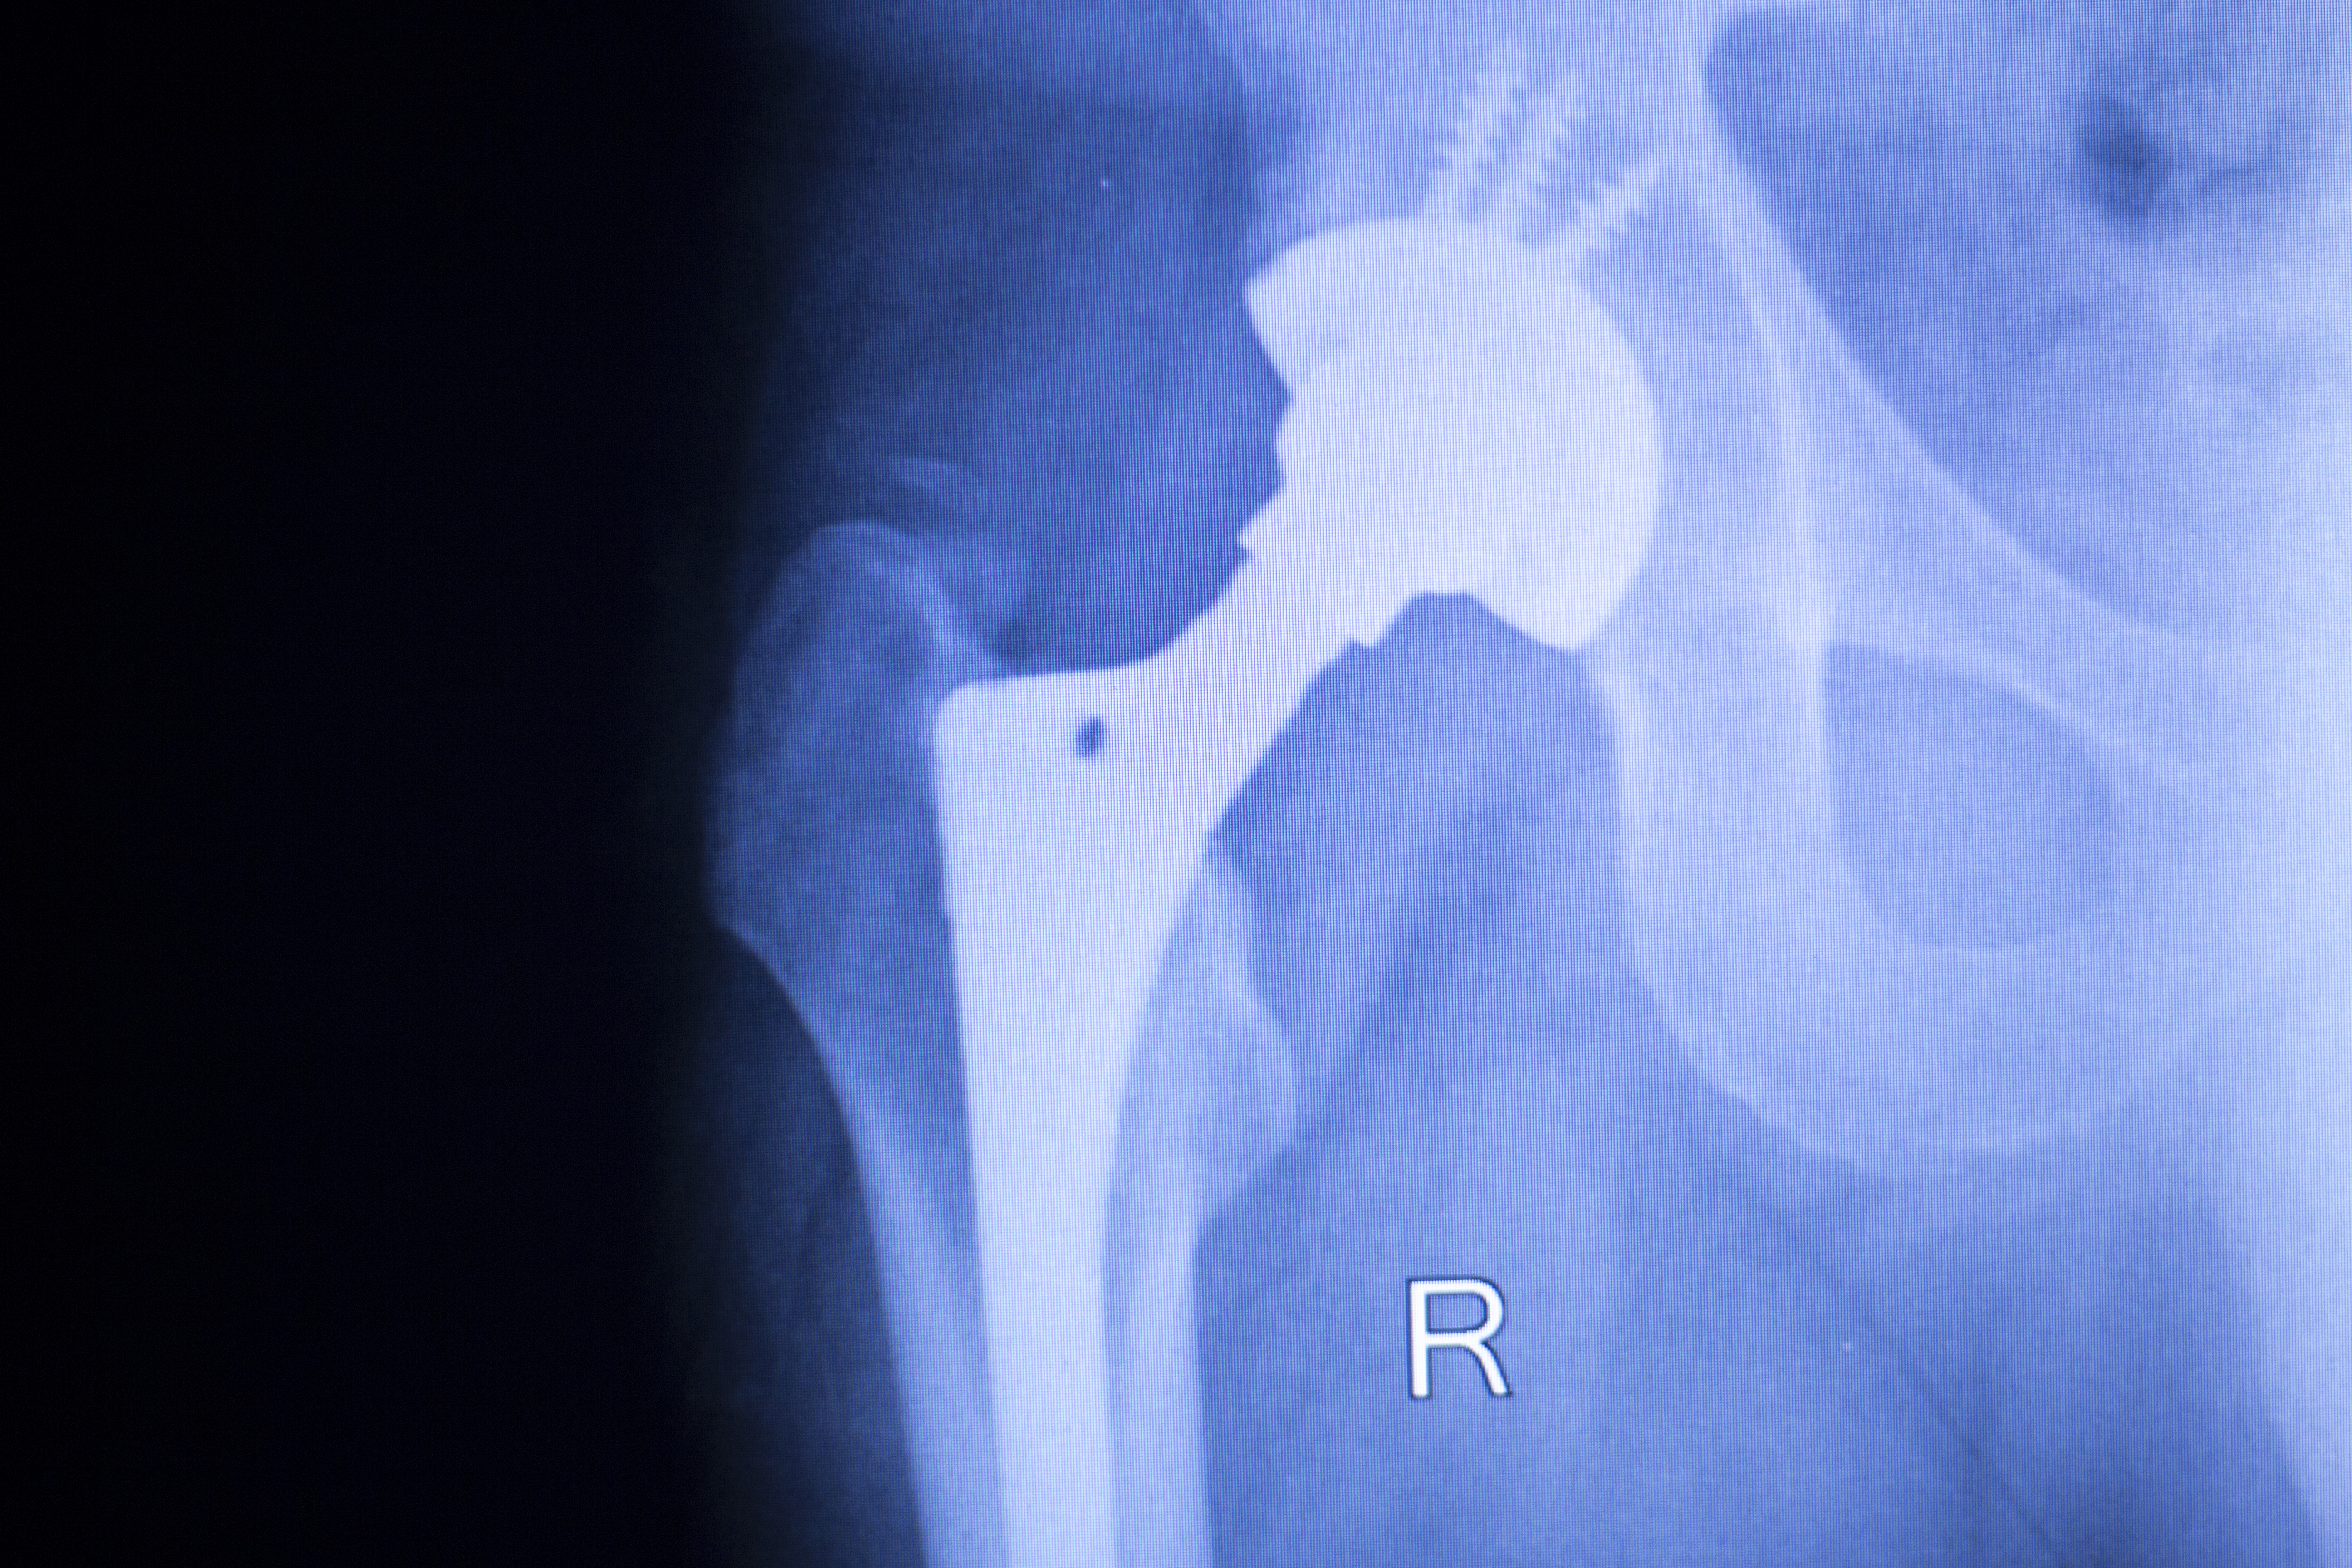

Photo: Colourbox

Particularly women over 75 years old and patients with hip fractures benefit from surgeons moving away from using uncemented femoral stems to instead using cemented femoral stems in hip replacement surgeries.

— The project was launched because we observed an increasing use of uncemented femoral stems in Norway. This was despite all recent studies showing that the risk of reoperations is higher when these stems are used compared to when cemented stems are used. The risk is particularly high for sustaining fractures around prostheses, which leads to major reoperations. The risk is especially high for the oldest patients, particularly for women over 75 years old and for patients with hip fractures, says Jan-Erik Gjertsen.

International guidelines recommend the use of cemented femoral stems for patients with hip fractures. Nevertheless, there were significant differences between hospitals in Norway before the project was initiated. At some hospitals, only cemented stems were used when operating on patients in the risk group. At other hospitals, however, only, or almost exclusively, uncemented stems were used.

— The results showed that the proportion of cemented femoral stems used in the treatment of the patient groups included in the project increased at the participating hospitals. For total hip replacements, it rose from 26% to 80%, and for hemiarthroplasty (for hip fractures) from 27% to 91%, says Gjertsen.

By using cemented femoral stems, the need for further surgery was also reduced. At the hospitals that participated in the project, the proportion of reoperations decreased from 3.7% to 2.1% for total prostheses, and from 5.9% to 3.3% for hemi-prostheses. This also resulted in better long-term outcomes and increased patient safety for a vulnerable group.

He also points out that uncemented femoral stems have good results in younger patients and are still used in this patient group. Therefore, there is no reason to switch to cemented stems for all patients.